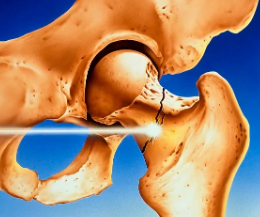

髋部骨折是老年人最严重的骨质疏松性骨折,具有高致残率和致死率。手术技术的提高和多学科协作管理模式对改善患者预后具有重要作用,也对围术期护理提出了更高要求。患者整体功能衰退、器官合并症增多、麻醉及手术对机体储备的二次打击使护理难度增加,且我国尚缺乏对于老年髋部骨折患者围术期护理的规范来指导临床实践。因此,中华护理学会骨科护理专业委员会组织相关专家,基于循证医学方法,制订《老年髋部骨折围术期护理临床实践专家共识(2023版)》,围绕老年髋部骨折围术期健康教育、病情监测与观察、并发症风险评估与预防、康复训练等方面提出11条推荐意见,以指导临床实践,提升围术期护理质量,改善老年髋部骨折患者预后。